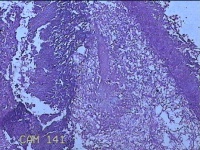

右侧窦腔内容物

性别

男

年龄

49岁

临床诊断

1.慢性鼻窦炎 2.鼻中隔偏曲 3.变应性鼻炎

一般病史

鼻塞、脓涕2月,加重伴涕中带血1周。

标本名称

大体所见

灰白暗红色不规则碎组织1.5x1.3x0.3cm一堆。

图1